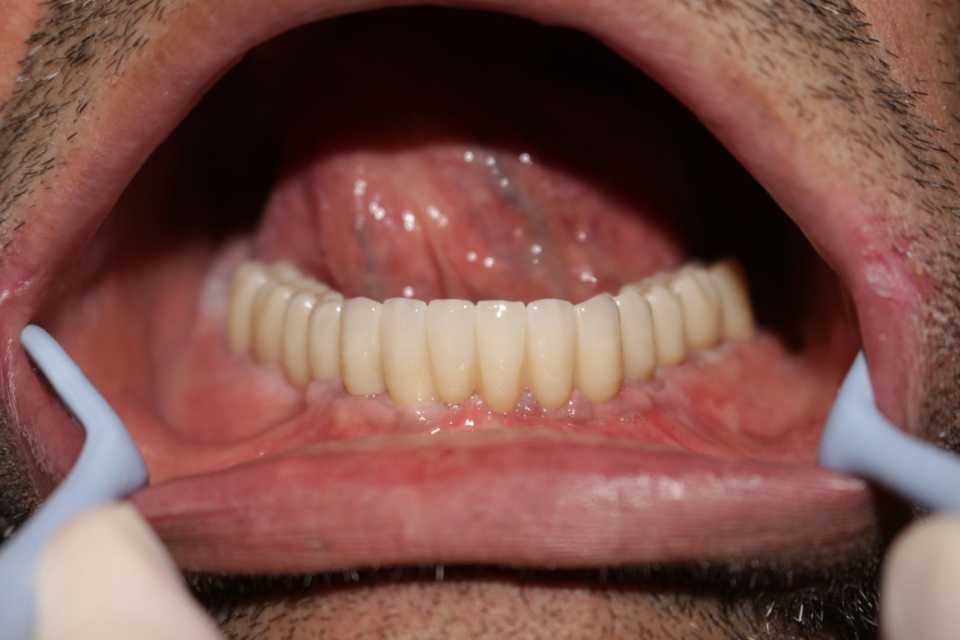

Reabilitare orală cu implanturi dentare Paltop, protezate cu lucrare insurubabila fixa din ceramica pe suport de zirconiu

Cazul 64: All on 6

A doua etapă – la aproximativ 5 săptămâni de la prima intervenție, implanturile sunt protezate printr-o lucrare fixă, înșurubabilă, din ceramică pe suport de zirconiu (preț: 1.500 lei per element).